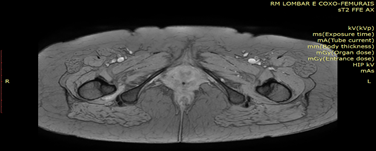

Female patient, 59 years old, followed in Rheumatology for Rheumatoid Arthritis since she was 38 years old. She went to the Rheumatology appointment due to pain, with limitation in abduction, internal and external rotations of the right coxofemoral joint and changes in gait pattern. MRI of the hip joints was requested, which revealed a significant reduction in the space between the lesser trochanter and the ischial tuberosity (Figure 1), with a significant change in the MRI signal of the right quadratus femoris muscle, which presents SPAIR hypersignal translating edema (Figure 2). These aspects are compatible with right ischiofemoral impingement. Rest, analgesic treatment and Physiatrist appointment were recommended. The patient is undergoing physiotherapy. It was prescribed ultrasound, laser, massage, pelvic muscle strengthening and stretching.

Figure 2 MRI of the hip joints identifies edema in the right quadratus femoris muscle.